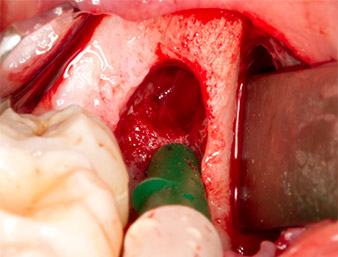

Um den Wurzelrest gewebeschonend frei zu präparieren, kam ein weiteres Instrument zum Einsatz (Piezomed S2), das primär für die Präparation des lateralen Fensters bei Sinusboden-Augmentationen indiziert ist. Zusätzlich wurden mit der diamantierten Kugel scharfe Knochenkanten geglättet (Abb. 6 und 7). Alle eingesetzten Piezomed-Aufsätze arbeiteten mit der jeweiligen automatischen Standardeinstellung ohne Booster-Funktion.

Piezomed S2

Abb. 6: Mit einem diamantierten kugelförmigen Instrument (Piezomed S2) wird der Wurzelrest vorsichtig frei präpariert, Knochenkanten werden geglättet.

Wurzelrest 38

Abb. 7: Der Wurzelrest 38 ist in seiner Alveole gut dargestellt für die nachfolgende Entfernung.